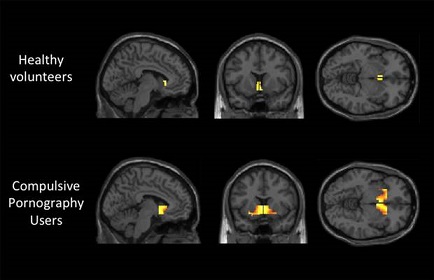

The series, which inspired this post, entitled Your Brain on Porn was put together by Gary Wilson and Marnia Robinson to explain just that. They do a wonderful job of breaking down the causes and effects of pornography as an addiction.

The Coolidge effect extrapolates to cases where lab rats have died of exhaustion because of the reintroduction of novel partners. pornography allows for the same amount of “New partners” because, as I mentioned above, there are so many video partners to choose from. It turns out that the limbic system of the brain plays a major role in the Coolidge effect.

Chemicals turn on and off certain parts of the brain. The main chemical, or neurotransmitter, that turns on the reward circuit is dopamine. The reward circuit is the engine, and dopamine is the gas.